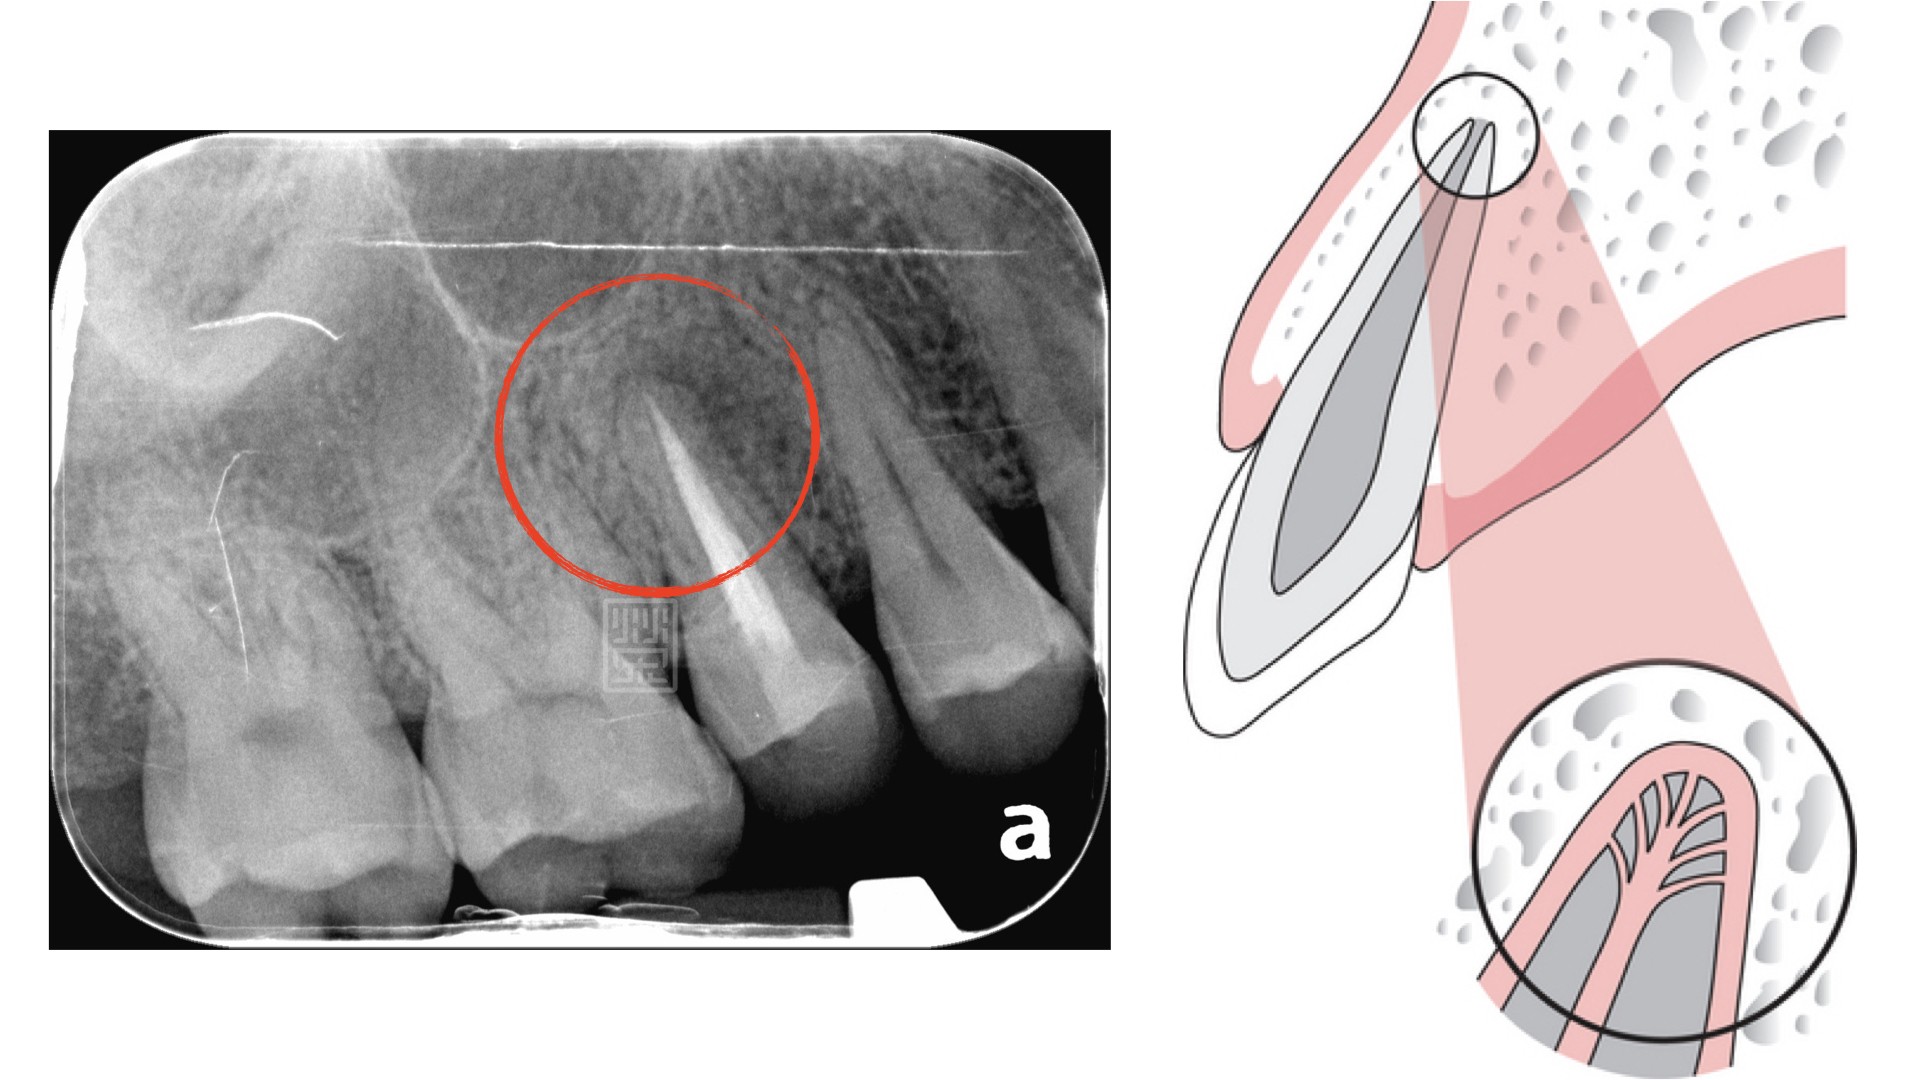

小臼齒牙根尖處,有部分未充填,並且牙根尖周圍有骨頭受傷的跡象。

為什麼差一點點,就會有這麼大的影響呢?因為牙髓腔中原本是由牙髓組織填滿,但是並不是一條水管的構造,比較像是樹枝分布,特別是在牙根尖5毫米處,如果有未清創或是未封填的區域,長期下來細菌滋生,等到細菌數增加,就會傷害牙根周圍組織,進而造成腫脹與疼痛。

為什麼差一點點,就會有這麼大的影響呢?因為牙髓腔中原本是由牙髓組織填滿,但是並不是一條水管的構造,比較像是樹枝分布,特別是在牙根尖5毫米處,如果有未清創或是未封填的區域,長期下來細菌滋生,等到細菌數增加,就會傷害牙根周圍組織,進而造成腫脹與疼痛。